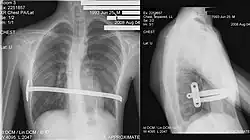

![]() X-Ray of a 15-year-old male after undergoing the procedure | |

Through two small incisions in the side of the chest, an introducer is pushed along posterior to the sternum and ribs, and anterior to the heart and lungs. Then a concave stainless steel bar is slipped under the sternum, through the incisions in the side of the chest. A third, smaller incision is made to insert a thoracoscope (small camera) used to help guide the bar. Taller patients, older patients, or patients requiring extensive correction may receive two or more bars. All bars may be placed through two incisions or additional incisions may be made. The bar is then flipped, and the sternum pops out. To support the bar and keep it in place, a metal plate called a stabilizer may be inserted with the bar on one side of the torso. PDS sutures may also be used in addition to the stabilizer. The stabilizer fits around the bar and into the ribcage. The bar and stabilizer are secured with sutures that dissolve in about six months.